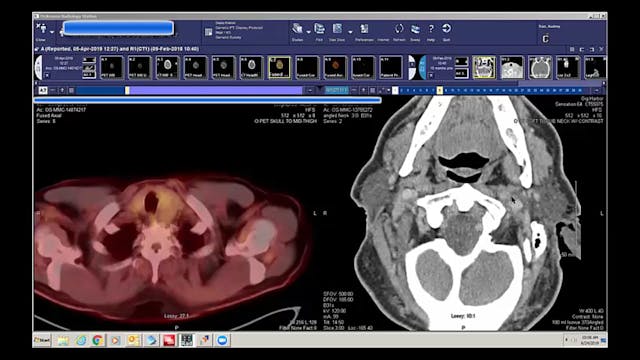

08/06/19 - Dr. Kenneth Hu - Radiation Oncology - Head and Neck US

Chartrounds US - Head and Neck Cancer